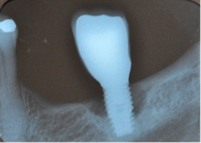

Temprana: Profundidad de sondaje >4 mm, con sangrado y/o supuración en >2 sitios del implante y pérdida ósea < 25% del largo del implante (Fig. 2)